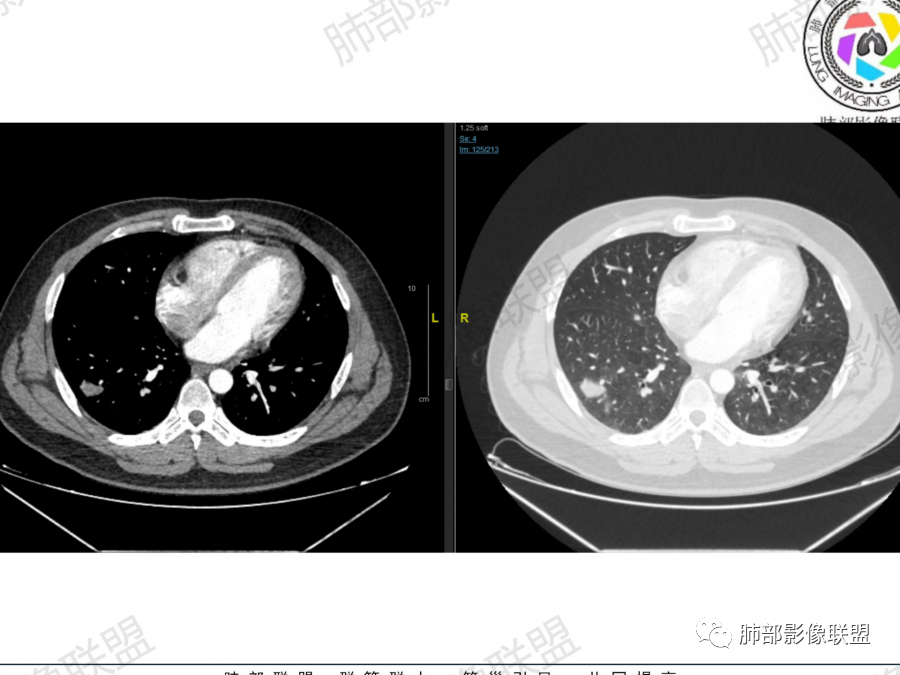

宇宙

右肺上叶及下叶胸膜下多发结节,上叶结节融合,强化均匀,其内支气管血管穿行,下叶外基底段胸膜下结节近端支气管进入后堵塞,考虑肉芽肿病变,隐球菌可能大,鉴别淋巴瘤

张延军

右肺上叶结节,内血管穿行正常,类似血管造影征,下叶病变贴于胸膜下病变,气管于近段阻塞,结合铁蛋白明显升高,考虑淋巴瘤

王秀仙

右肺上叶肿块,内支气管穿行扩张,血管显示清楚。右肺下叶多发结节,部分长轴平行于胸膜,部分结节周围见磨玻璃晕征。考虑一元淋巴瘤,二元,右肺上叶淋巴瘤,下叶隐球菌。

1.右上肺团块:分叶,不均性强化,其内支气管走行自然,增强血管影可见、清晰。

2.右下肺结节、实变:胸膜下,长轴平行胸膜。部分似有晕影。支气管进入后近段截断

2、右肺多发结节影,大者位于右肺上叶尖段,内可见空洞,空洞内壁欠规整,内可见分隔,余结节位于胸膜下、结节大小不等、形态相近,强化均匀,内部可见血管穿行,血管及支气管走行自然。结合临床及影像,符合隐球病。

2、隐球菌感染有时相性,初期的隐球菌感染周围有晕征,晕从多变少,或包裹,或吸收,结节实性区可迅速变大,后期(慢性期)的隐球菌周围无明显晕征,边界较清楚。本例病变发病一月, 为后期,晕征不明显。

总之,隐球菌卫星灶形态相似、可位于病变周围及远侧肺。与结核球的鉴别是:结核卫星灶、多形、多灶, 往往位于主病灶周围。本例卫星灶与“蘑菇兄弟”在右肺下叶,有提示作用。